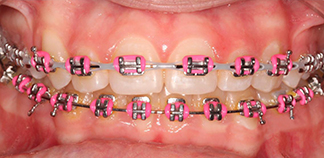

До лечения

Жалобы на скученность зубов.

Как лечили

Проведено ортодонтическое лечение на брекетах.

Лечащий врач

МАРЦИ Анастасия Викторовна